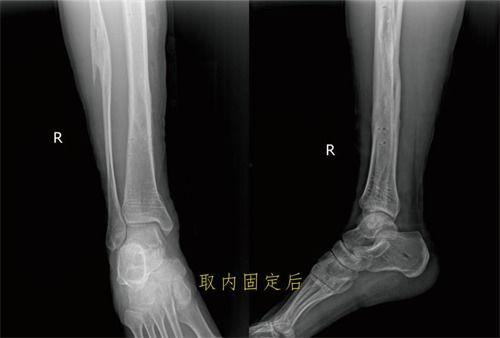

2. 胫腓骨骨折:胫腓骨骨折多发生在踝关节扭伤或跌倒时。